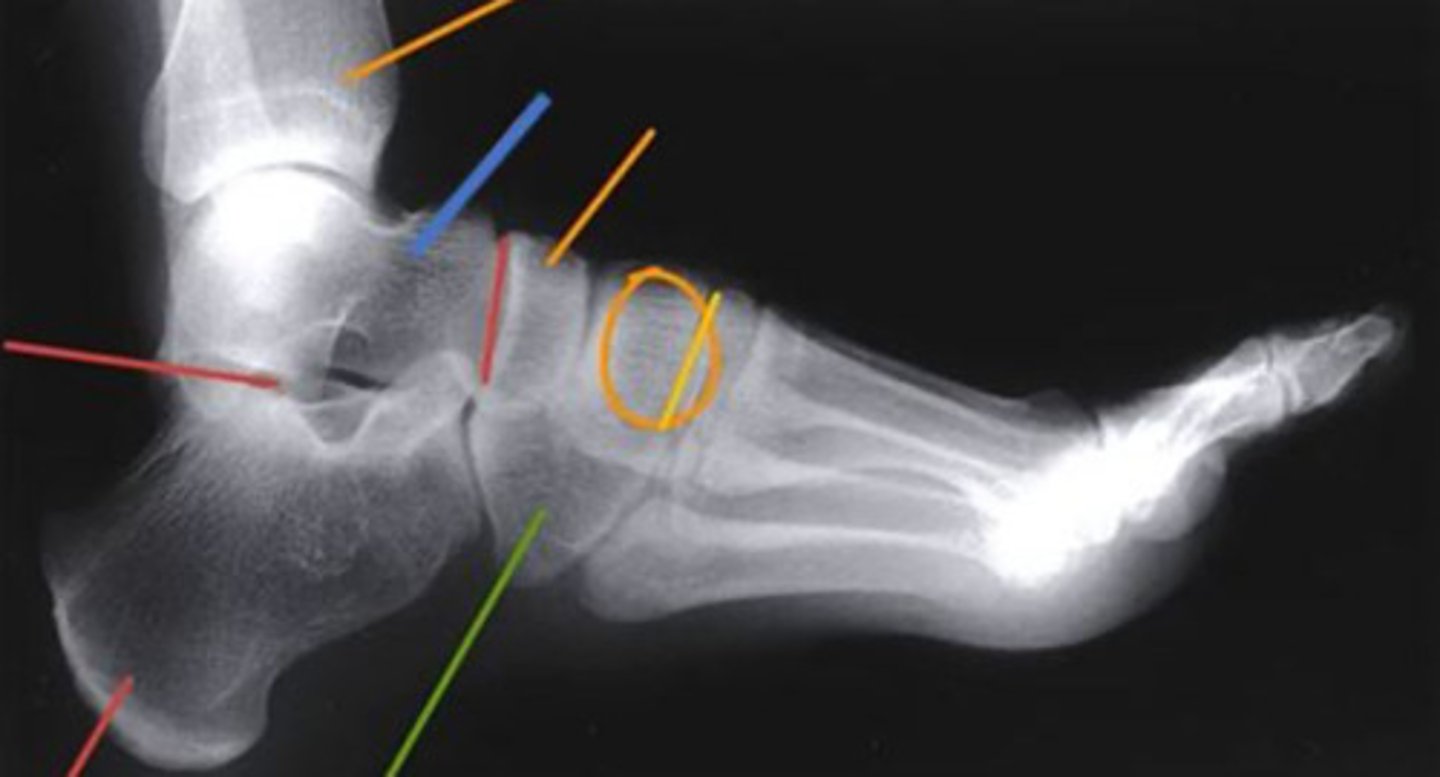

what radiograph view is this?

oblique

what radiograph view is shown here?

lateral

what do the orange circles in these radiographs indicate about the patient's injury to the anterior process of the calcaneus?

avulsion fracture

which structure of the foot is highlighted by the blue line?

talus